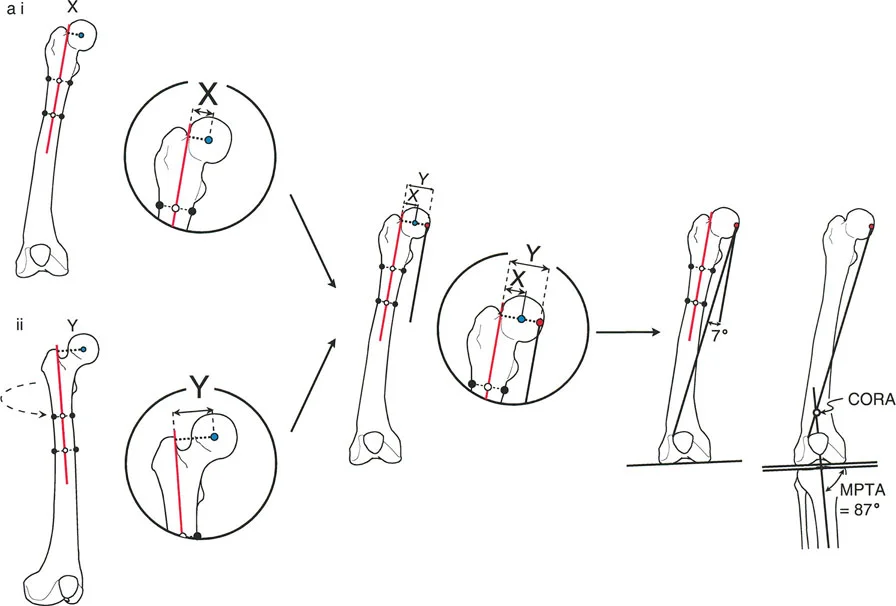

تحليل دوران الفخذ (Femoral Version Calculation)

يتطلب قياس زاوية دوران الفخذ (Femoral Version) صوراً إشعاعية خاصة تُعرف باسم "تحليل المستوى المائل". يحدد هذا التحليل مدى التواء عظم الفخذ حول محوره.

1. وضعية المريض: يتم الحصول على صورتين بالأشعة السينية (AP و Cross-table Lateral) لمفصل الورك مع توجيه صابونة الركبة للأمام تماماً (وضعية "الركبة للأمام").

2. التثبيت: من الضروري عدم تحريك أو تدوير الطرف بين الصورتين. بدلاً من ذلك، يتم تحريك جهاز الأشعة السينية للحصول على الصورة الجانبية.

3. القياس: يتم قياس زوايا محددة على كل صورة، ثم يتم استخدام هذه القياسات لحساب زاوية الدوران الفعلية.

يفضل الدكتور هطيف استخدام الطريقة المثلثية لحساب هذه الزاوية لضمان أعلى دقة ممكنة، خاصة عندما تكون الزوايا كبيرة.

تتم مقارنة الزاوية المحسوبة بالجانب الآخر السليم (إذا وجد) أو بالنطاق الطبيعي المعروف (عادة ما يتراوح بين 5° إلى 20° من النسخة الأمامية).

تحليل دوران قصبة الساق (Tibial Torsion Analysis)

يتبع تحليل دوران قصبة الساق (Tibial Torsion) منطقاً مشابهاً ولكنه يعتمد على معالم تشريحية مختلفة (الكاحلين). يحدد هذا التحليل مدى التواء عظم قصبة الساق.

1. بروتوكول التصوير: يتم الحصول على صورتين بالأشعة السينية (AP و Lateral) للكاحل مع توجيه صابونة الركبة للأمام.

2. القياس: يتم قياس المسافة العرضية بين الكاحل الإنسي والوحشي على كلتا الصورتين.

3. الرسم البياني: يتم رسم هذه القيم على رسم بياني للمستوى المائل لتحديد اتجاه مستوى الكاحلين.

4. المقارنة: تُقارن زاوية الدوران المحسوبة بالجانب الآخر السليم أو بالنطاق الفسيولوجي الطبيعي (عادة 15° ± 5° من الدوران الخارجي).

تحديد مستوى التشوه بدقة

إن تحديد المستوى الدقيق للتشوه الدوراني هو أحد أهم الخطوات في التخطيط الجراحي. على الرغم من أن الدوران هو تشوه زاوي في المستوى المستعرض، إلا أن موقعه على طول العظم (قريب من المفصل أو بعيد عنه) يؤثر بشكل كبير على كيفية تصحيحه وتأثيره على الأنسجة المحيطة.

- في حالات ما بعد الإصابة: يكون مستوى التشوه واضحاً عادة عند موقع الكسر الملتئم.

- في الحالات الخلقية أو التنموية: يتطلب تحديد مستوى التشوه استنتاجاً سريرياً دقيقاً يعتمد على تأثيره العميق على مسار العضلات والأوتار. يعتمد الدكتور هطيف على خبرته الواسعة في تقييم هذه الحالات لتحديد المستوى الأمثل لقطع العظم.